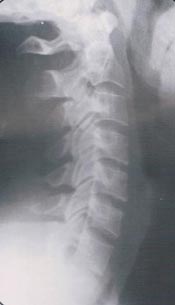

頭の重さを知っていますか?首の疲れと姿勢の関係